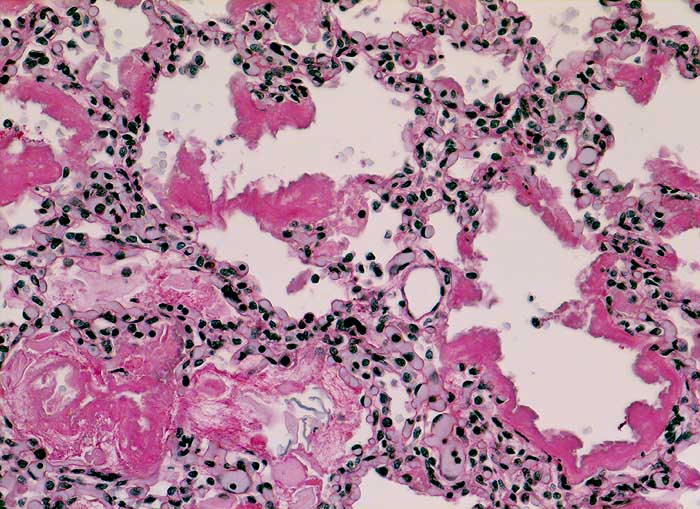

AP/ Hyaline-Membranen-Krankheit des Neugeborenen

Hyaline-Membranen-Krankheit des Neugeborenen

Lunge